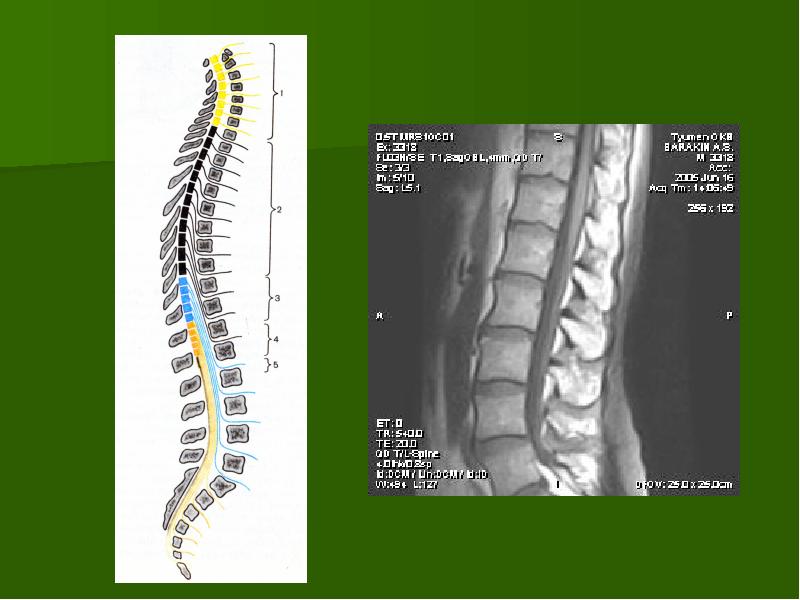

Отделы позвоночника для мрт схема фото и названия